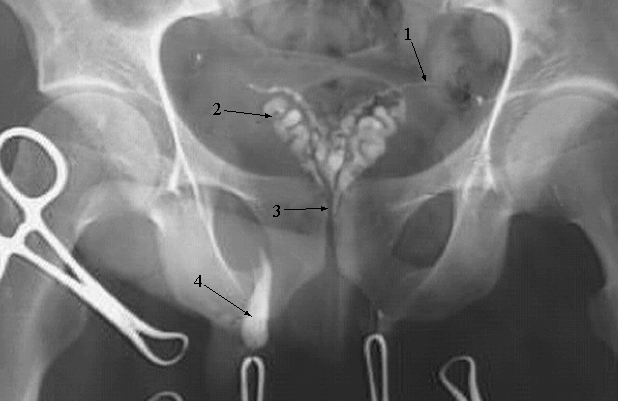

Pelvis & Perineum: Vasogram:

1. Ductus Deferens

2. Seminal Vesicle

3. Prostatic Urethra

4. Extravasation of contrast material